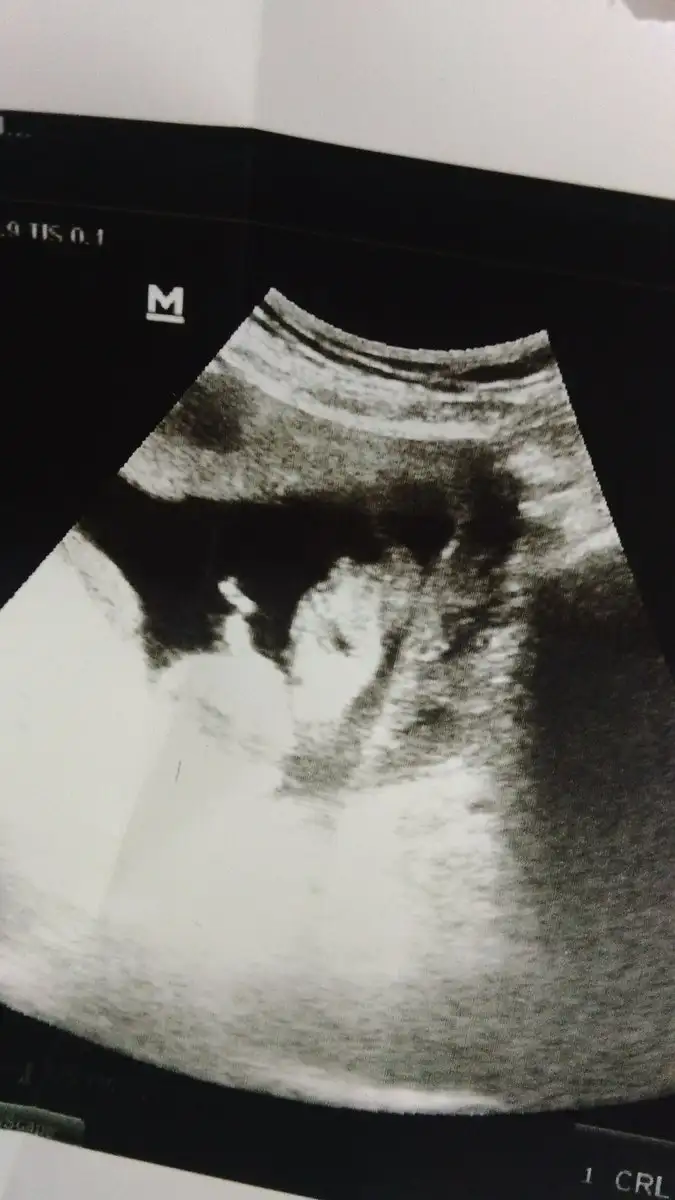

Atmıştm galibaCanim sen once hic ultrason fotosu atmismiydin bakayim bi

Bak bakalım :)Canim sen once hic ultrason fotosu atmismiydin bakayim bi

Burda kac haftalikBak bakalım :)

13 +1 yazıyor canımBurda kac haftalik

Meraktan sadece ama gozu acik annesi nasilda bakiyo onu fark ettim13 +1 yazıyor canım